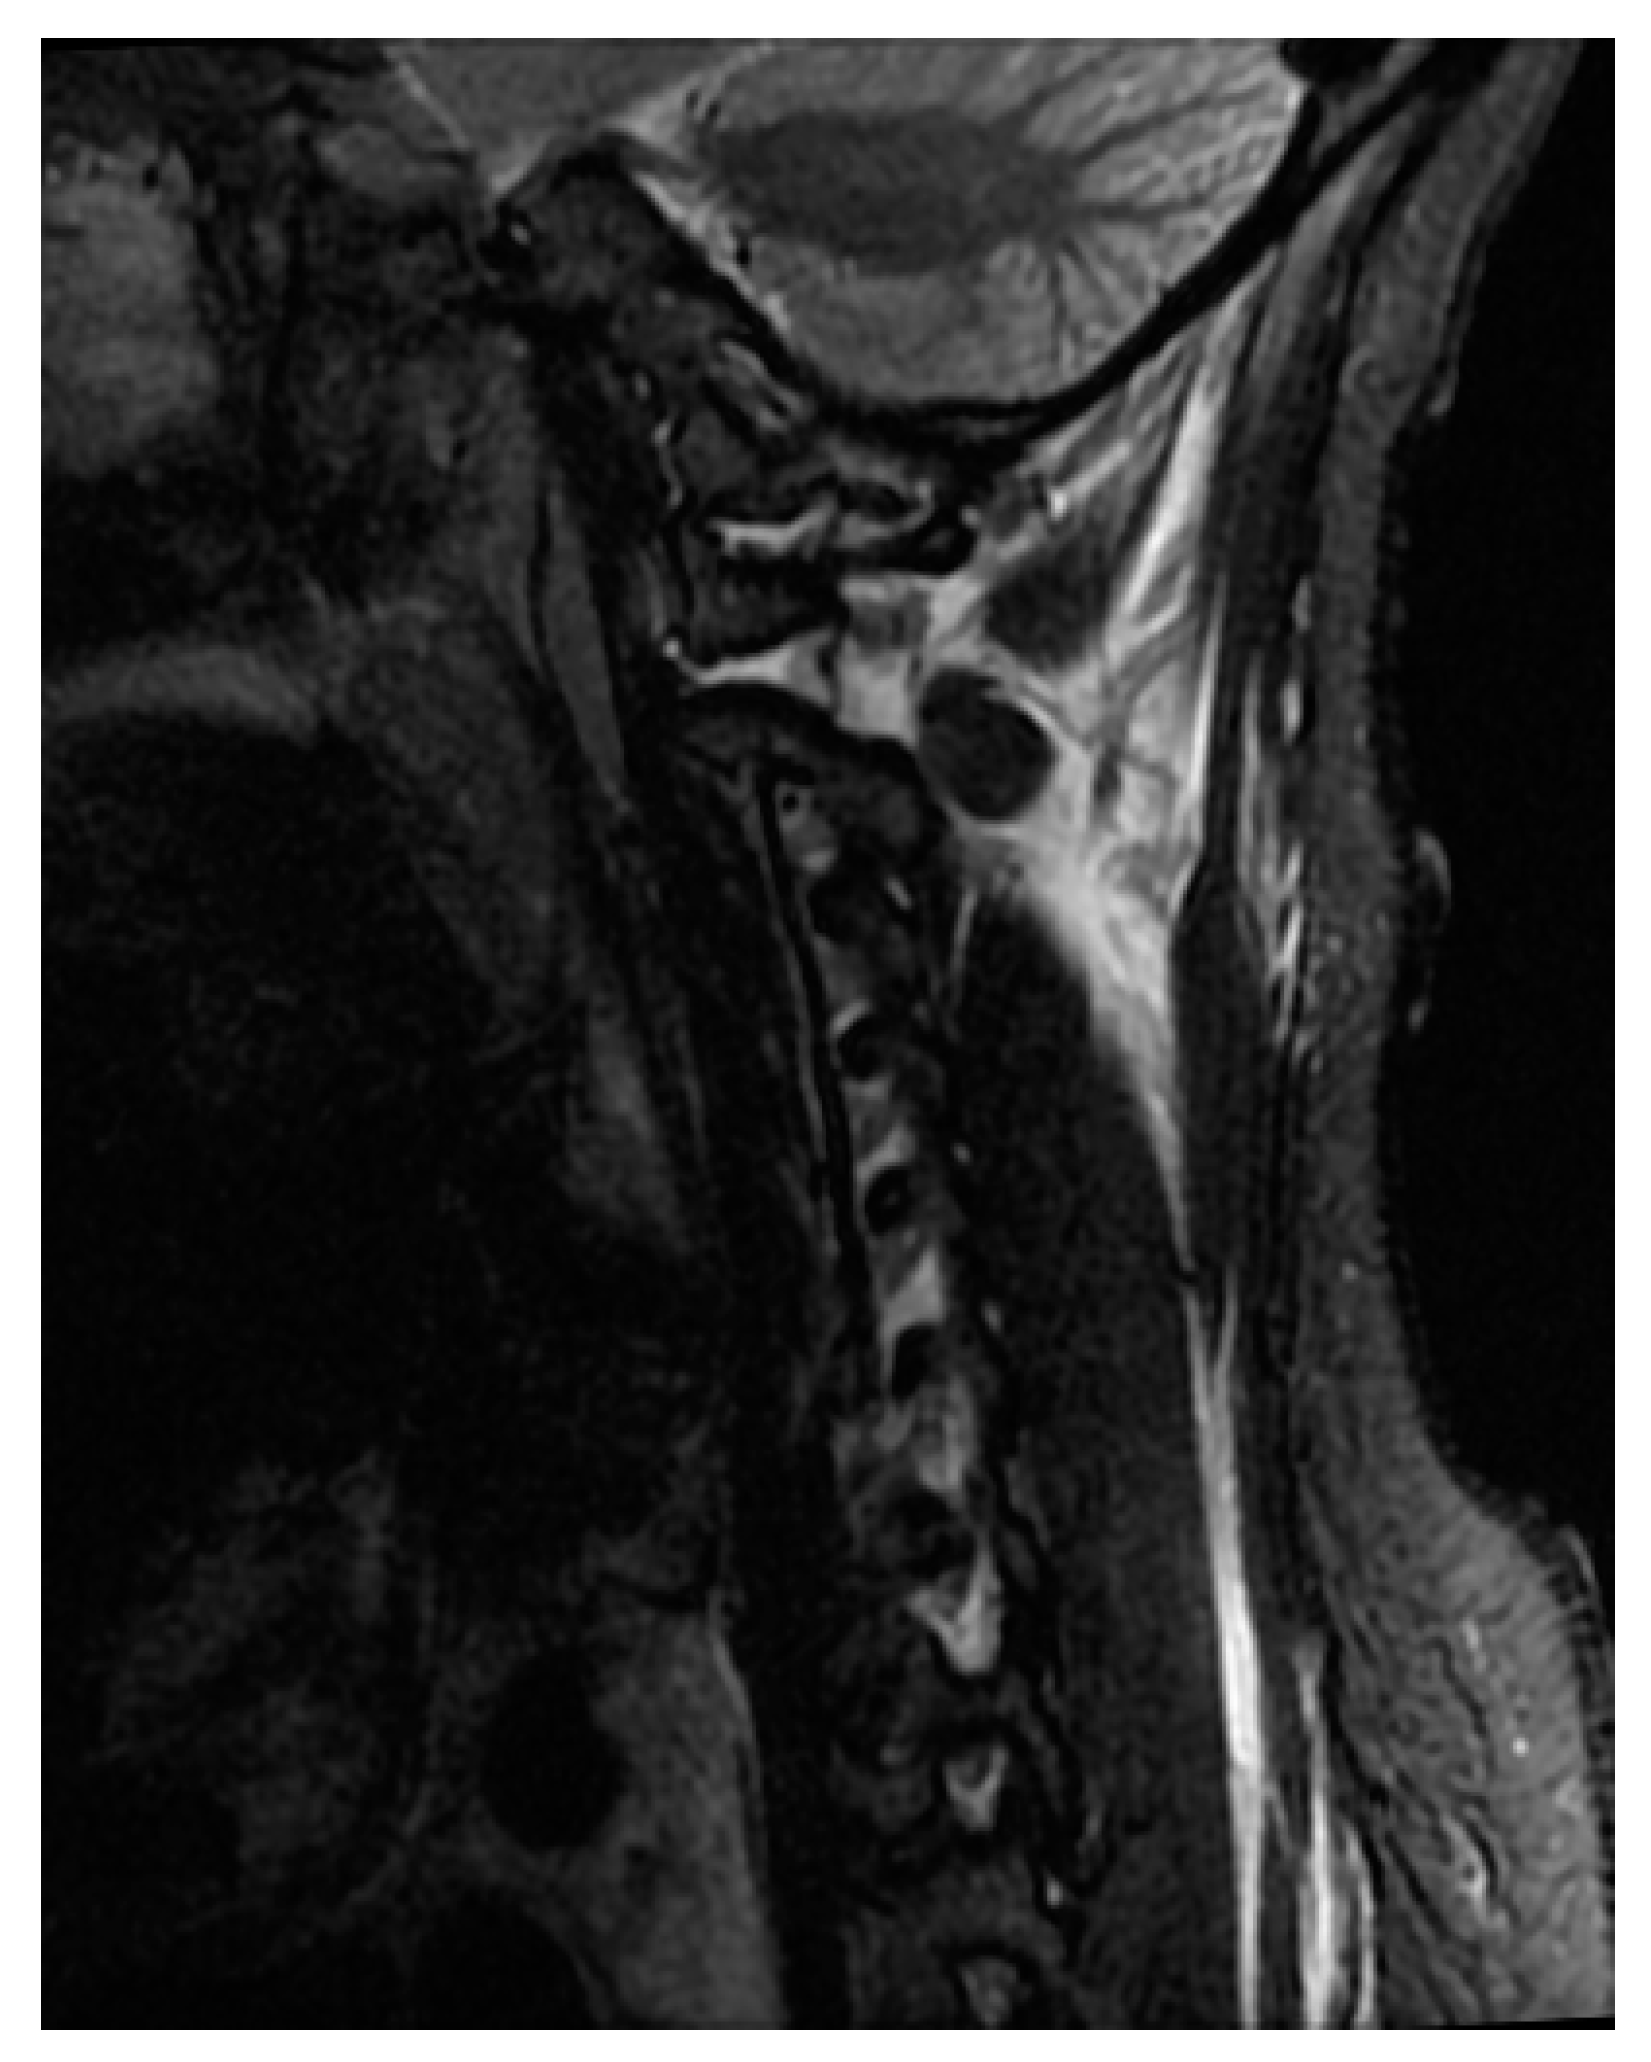

MRI is currently considered the gold standard imaging modality for the evaluation of patients with spinal cord injury and spinal trauma [20,21,22]. MRI has multiplanar capabilities with high-contrast resolution and is, therefore, capable of providing information regarding spinal cord compression, ligamentous instability (Figure 4), disk herniation, contusion, and hemorrhage (Figure 5), as well as injury to vertebral bodies and paraspinal tissues [23,24,25]. In a review done by Sliker et al. (2005) in patients with blunt trauma, the authors reported 22.7% ligamentous injury detection by MRI, of which 80.8% required treatment [26]. Despite the time taken to perform MRI, it is still recommended in the pre- and post-operative stages when feasible [27]. Not only is MRI noted to be safe, when protocols are followed, it also directly impacts clinical decisions for the surgeon [27].

Figure 4.

Sagittal view of STIR sequence of MRI shows signal changes in the C1/2 and C1/condyle joint.

Conventional MRI, both T1- and T2-weighted imaging, have limited prognostic value. Currently, T2-weighted imaging, as well as the short tau inversion recovery (STIR) sequence, are the most important sequences in acute spinal cord injury since they have high sensitivity to intramedullary pathology, and to acute injury/edema [28,29]. STIR images are sensitive in detecting edema within the spinal cord as well as the surrounding soft tissue and ligaments, with the advantage of providing more consistent fat suppression compared to fat-suppressed T2WI [30]. The presence of STIR signal within the spinal cord in combination with acute neurologic deficit and possible bony or ligamentous injury should be factors that aid in decision making for the spine surgeon [27].

T2-weighted MRI is sensitive to the paramagnetic effects of iron present in blood products. Intramedullary hemorrhage presents as an area of hypo-intensity on T2W imaging, and its presence has a prognostic implication (Figure 4) [28,31,32]. T2*W and susceptibility-weighted imaging (SWI) sequences are also used for the detection of intramedullary hemorrhage [33].